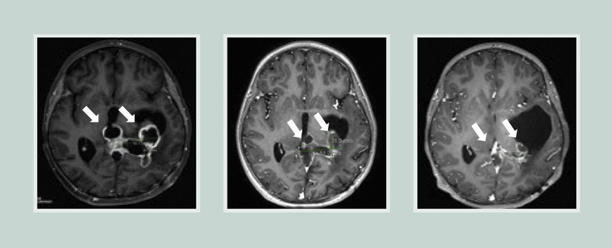

Called diffuse midline gliomas (DMGs), these deep-rooted brain tumors often develop in childhood, and there are currently no effective treatments available to tackle them.

One drug, called ONC201, has shown promise for other kinds of tumors in the nervous system. Following research suggesting it could be effective against a DMG with a specific mutation, an international team of researchers has carried out a trial putting the dopamine receptor blocker to the test.

Previously, ONC201 had shown promise when treating DMGs with the H3K27M mutation. Earlier studies also showed that the compound could pass through the blood-brain barrier, a built-in biological safety net for our brains that makes delivering drugs to brain tumors particularly difficult.